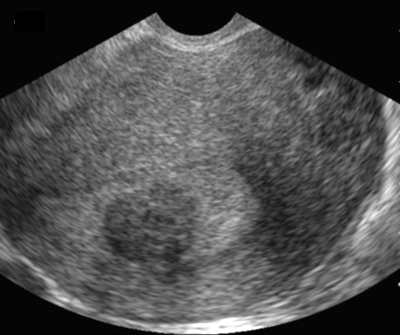

Myome sous-muqueux hypoéchogène par rapport à l’endomètre. Coupe sagittale (Cliché : Dr. C. TALMANT)